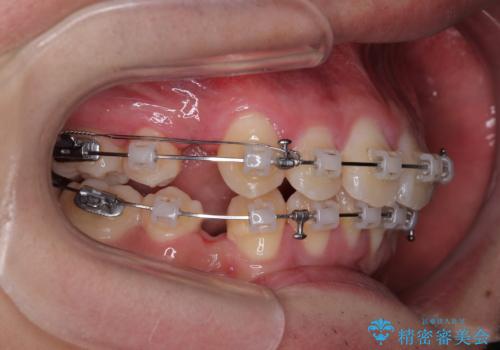

- クリアブラケット

特に前歯のデコボコが顕著であり、上下左右第一小臼歯の4本を抜歯し、ワイヤー装置を使用して咬み合わせ高さを改善しながら、歯列を整えて行くこととしました。

移動が順調に進み、1年半の短期間で治療を終えることができました。